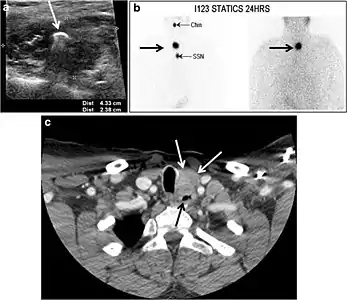

Fig. 7. A 51-year-old female patient post total thyroidectomy for PTC with elevated thyroglobulin measurement. an Axial non-enhanced CT scan of the neck at the level of the thyroid bed demonstrates a well-defined, rounded, homogenously dense soft tissue situated between the trachea and left internal jugular vein (white arrow). b Transverse ultrasound image of the neck demonstrates a well-defined, homogeneous, hypoechoic soft tissue nodule measuring 6 mm (white arrow) with no detected micro-calcifications. Biopsy showed a predominantly residual normal thyroid tissue with micro-foci of PTC.[1]

Fig. 8. A 48-year-old male patient post total thyroidectomy with PTC recurrence. a Transverse greyscale ultrasound of the neck demonstrates a left thyroid bed heterogeneous, predominantly hypoechoic irregular lesion with calcifications (white arrow). b A spot image of iodine 123 total body scan of the neck demonstrate a focus of abnormal radiotracer uptake at the left thyroid bed (Black arrows) between the annotated markers. c Enhanced axial CT scan of the neck demonstrates an enhancing large left thyroid bed mass (white arrow) with no calcifications. The lesion exerts a mass effect on the oesophagus (black arrow) and is inseparable from the trachea.[1]

Fig. 17. Ectopic thyroid on the left parotid gland with a palpable left parotid mass in a 69-year-old male patient. a, b Axial and coronal enhanced neck CT scan demonstrates well-defined homogeneous enhancing mass (white arrows) within the left parotid gland with preserved surrounding fat planes. It also shows a normal thyroid in normal position in the lower neck. c Image taken 20 minutes after 5 mCi injected Tc99m-Pertechnetate shows normal thyroid uptake of tracer and physiological uptake in the salivary glands (short black arrow). There is a distinct focus of abnormal tracer accumulation in the left parotid/submandibular region. Patient was given lemon juice with evident normal washout from the salivary glands and relative retention by this abnormal focus (long black arrow).[1]

Fig. 18. Lingular thyroid in a 33-year-old male who presented with oropharyngeal bleeding. an Axial enhanced neck CT scan at the level of mandible demonstrates a 3 × 3 × 3.4 cm round, partly well-delineated, heterogeneously enhancing lesion (white arrow). It is predominantly on the left side of the oropharynx and to some extent at the mid part of the base of the tongue. The thyroid gland was normal (not shown). b Image of the anterior face and neck taken 20 minutes after Tc99m-Pertechnetate injection shows absent thyroid radiotracer uptake in normal thyroid anatomical location (black short arrows). There is an area of increased uptake (long black arrows) corresponding to the posterior tongue mass identified on CT scan.[1]